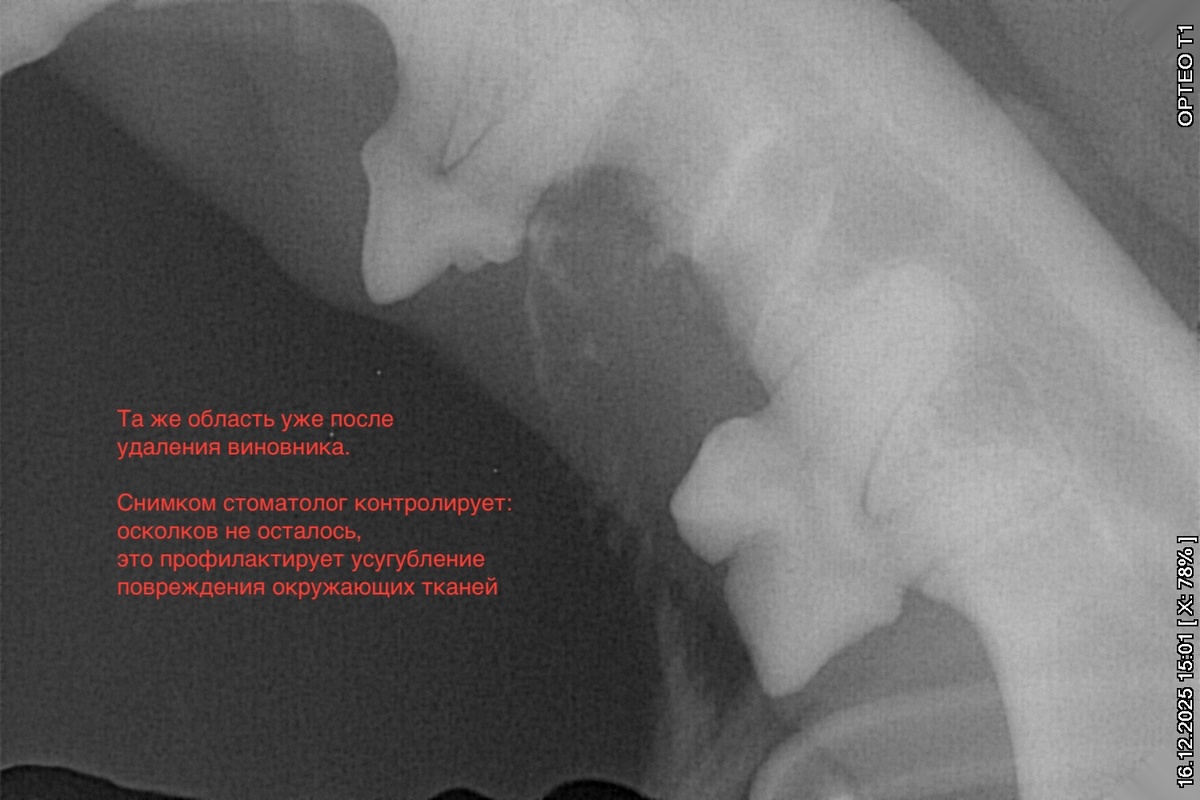

Мне направили кучу снимков дентального рентгена*, всё показали, пригласили на повторный прием через год. Стоматолог была крайне уверена в проведенных вмешательствах и восстановлении, я тоже. Но все равно держала в голове, что может понадобиться приехать повторно в ближайшее время. Послеоперационные риски никто не отменял.

*в ветеринарии это оборудование для метода диагностики, при котором делаются рентгеновские снимки конкретных зубов и прилежащих к ним структур. Только так можно увидеть, что же с корнями зубов там, где точечно усилено воспаление десны... Затронут ли пародонт и насколько – иначе не увидеть при относительно несильном поражении.